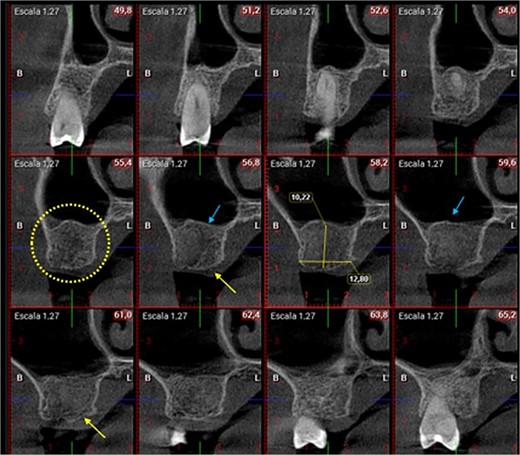

A 56-year-old female patient without any systemic diseases was referred by otolaryngology for evaluation by oral surgery due to presenting pain on the left side of the face for two weeks. The patient’s first molar presented a wide restoration (Fig. 1). This molar had undergone endodontic treatment some years ago. The CT scan showed a hyperdense left maxillary sinus almost entirely with loss of continuity of the maxillary sinus floor at the level of the left upper first molar involving the furcation zone, it is evident an oroantral communication of 7 mm (Fig. 2). The patient referred to spontaneous pain during chewing. Based on the CT scan and the clinical findings, pharmacological management was indicated with oral antihistamine 10 mg every 24 hours for 10 days, Moxifloxacin 400 mg every 24 hours, and scheduled extraction with oroantral communication closure with collagen sponge on the third day after starting the antibiotic, which will be used for a total of 10 days. The patient agreed to sign an informed consent file to make the technique to extraction and close the oroantral communication.

A control appointment was made 8 days later, and the scar tissue with slight erythema on the edges of the alveolus was observed (Fig. 6). The patient was asymptomatic, and the membrane was in position to cover the entire alveolus. After the fourth week, granulation tissue was observed covering almost the entire alveolus, and an area was observed where the membrane found below this granulation tissue could be seen (Fig. 7). About 3 months after surgery, healed soft tissue was observed, and a CT scan was requested, where the maxillary sinus was observed without evidence of pathologies and hypodense alveolar bone compatible with immature bone in the process of calcification (Fig. 8). After 6 months, keratinized tissue and a completely healed alveolus were observed (Fig. 9), and cone beam computed tomography (CBCT) was requested to evaluate the results and see the possibility of placing an implant. In the CT scan, continuous sinus and alveolar cortex were observed with an image compatible with bone in the healing process (Fig. 10).